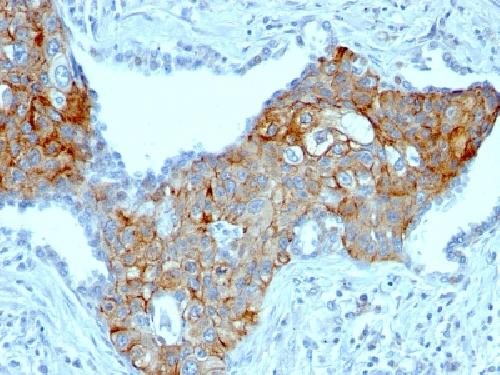

TRIM29 (Lung Squamous Cell Carcinoma Marker) Antibody

| Description | TRIM29 (Lung Squamous Cell Carcinoma Marker); Clone TRIM29/1041 (Concentrate) |

| Application notes | A431 cells. Tonsil or Squamous cell carcinoma. |